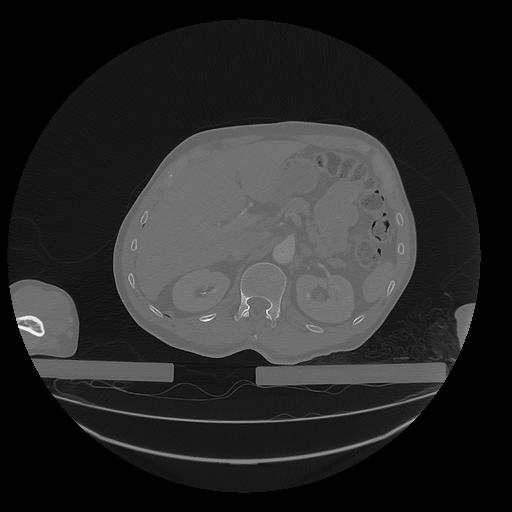

31 PULMON,CE,Vol,1.0,PULMON,,